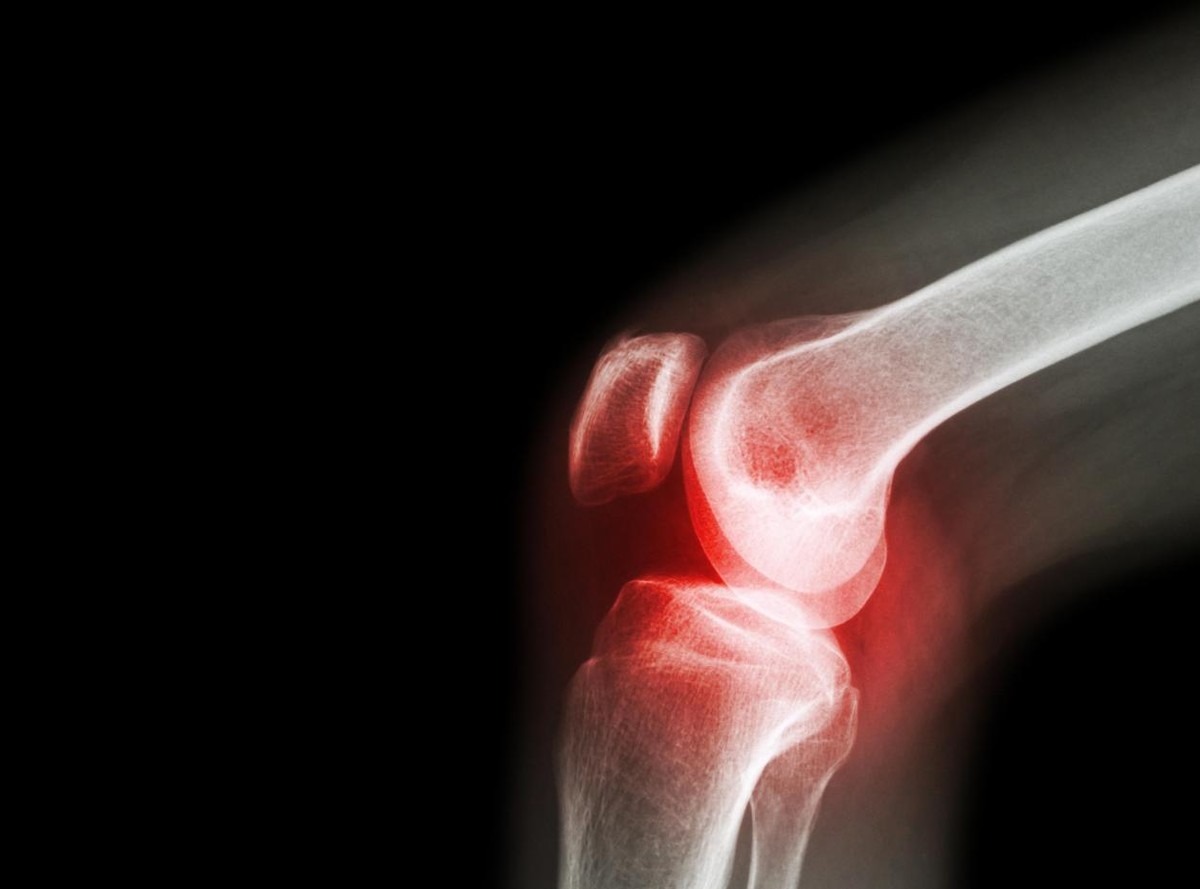

骨关节炎又名老年性关节炎,是一种因为关节老化、蜕变、磨损加重而出现的病理现象。

骨关节炎早期症状隐匿,类似风湿,常出现轻微疼痛,且与天气变化有关。另外患者还有晨僵、肿痛、关节作响等非典型症状。